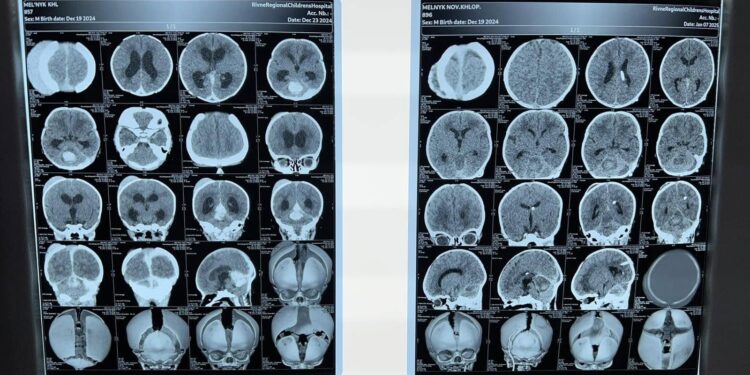

Малюк, якого назвали Миколкою, з’явився на світ 19 грудня. На четверту добу життя дитину госпіталізували до неонатального центру з діагнозом оклюзійна гідроцефалія невідомого походження.

Фахівці Рівненської обласної дитячої лікарні провели необхідні обстеження та встановили причину патології — крововилив у задню черепну ямку. Завдяки злагодженій роботі медиків вдалося врятувати життя дитини.

Лікар-нейрохірург дитячий Сергій Романчук невідкладно провів операцію — вентрикулоперитонеостомію по ургенним показав на шосту добу життя малюка, що стала рятівною для маленького пацієнта. Без цього оперативного втручання шанси на здорове життя та уникнення важкої інвалідності були практично відсутні. Під час операції професійну анестезіологічну допомогу надавала дитячий лікар-анестезіолог Корнуелла Мудра.